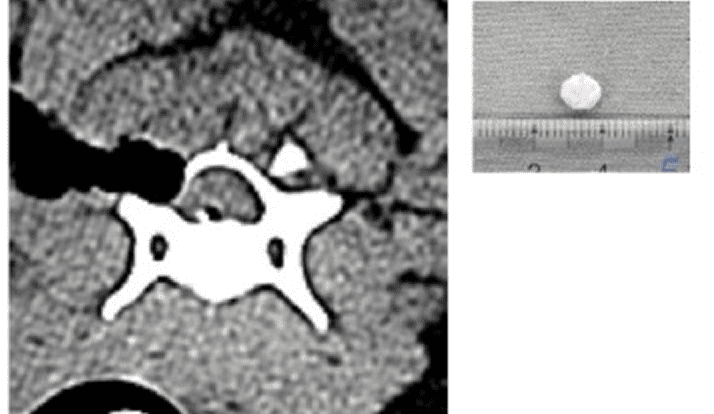

術前CT・MRI検査

静脈洞直上に椎間板物質の逸脱を疑う。静脈洞から出血する可能性が高いため片側椎弓切除術にて椎間板物質の摘出実施

術後CT

椎間板物質の摘出(一塊で堅い物質が摘出された)